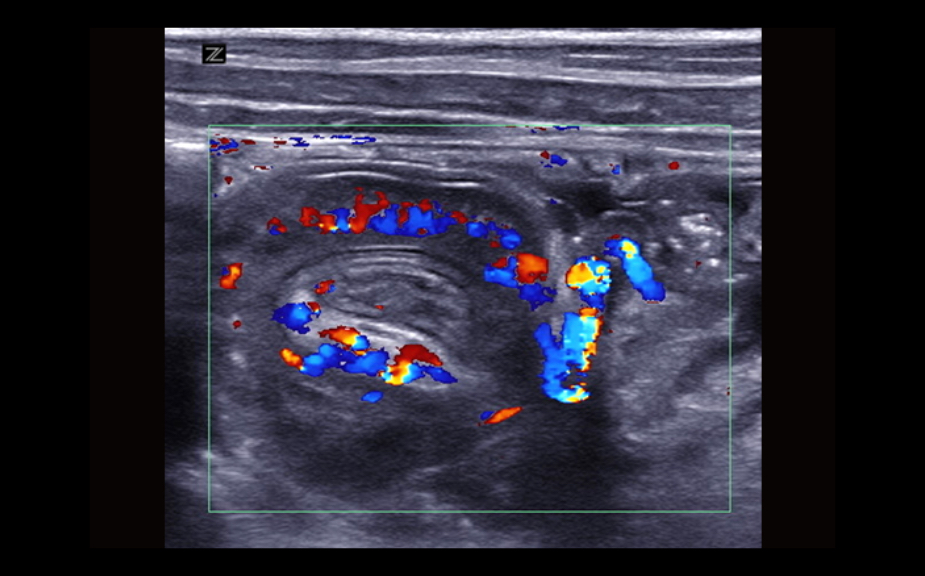

Equipado con software patentado con base en tecnolog├Ła ZONE?Sonography? (ZST),?el Z.One PRO proporciona toma de im├Īgenes Doppler y Modo-B detalladas ├│ptimamente para pacientes, sin importar la complexi├│n del cuerpo, ayudando a asegurar un diagn├│stico confiable.

A trav├®s de una amplia gama de aplicaciones, el Z.One PRO es la soluci├│n de ultrasonido para sus exigentes desaf├Łos cl├Łnicos.

- Insuperable calidad de imagen en todas las aplicaciones